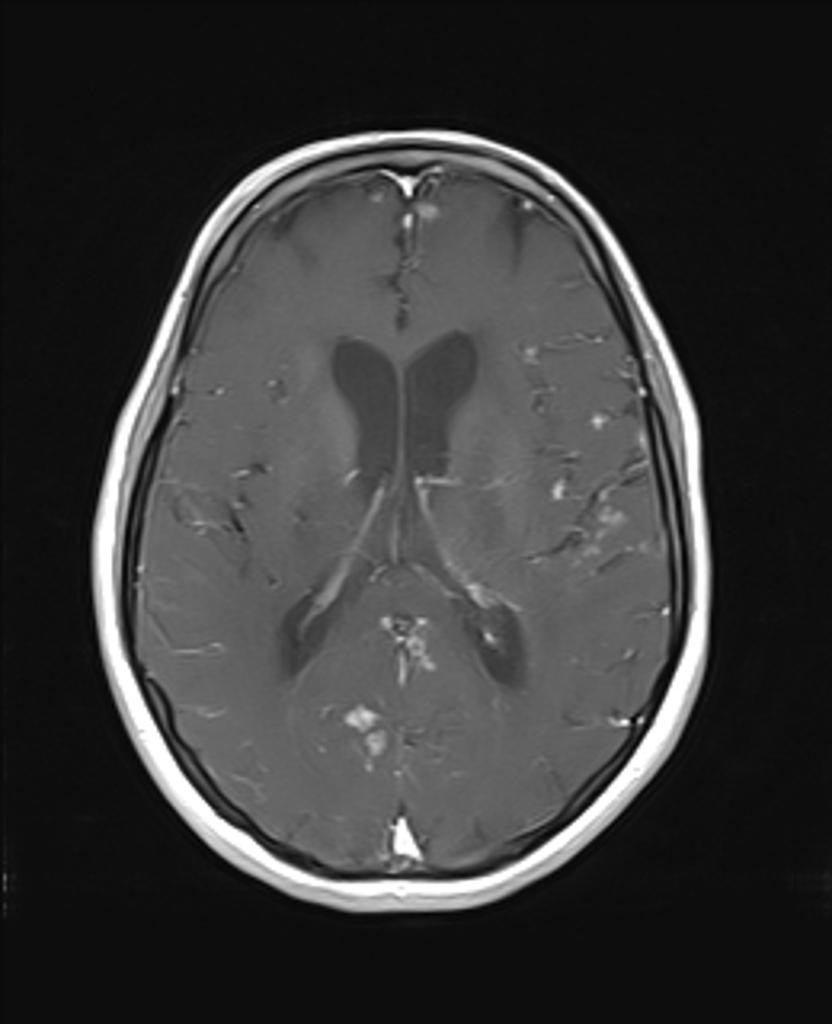

Toxoplasmose

• Toxoplasma gondii

• Bénigne chez l’immuno compétent

• Gravissime chez l’immuno déprimé

• Forme encéphalitique (fièvre, céphalées, confusion)

• Forme focale : déficit, comitialité

• Possibilité d’atteinte médullaire

• PL : lymphocytose modérée

IRM

• Forme pseudo-encéphalitique (rare)

• Forme nodulaire pseudo tumorale (fréquente)

• Lésion élémentaire

• Nodule hypoT1

• HyperT2

• Réhaussé en périphérie par le PDC

• Entouré d’œdème

• Lésions multiples disséminées sus et sous tentorielle

• Forme hémorragique classique notamment après traitement